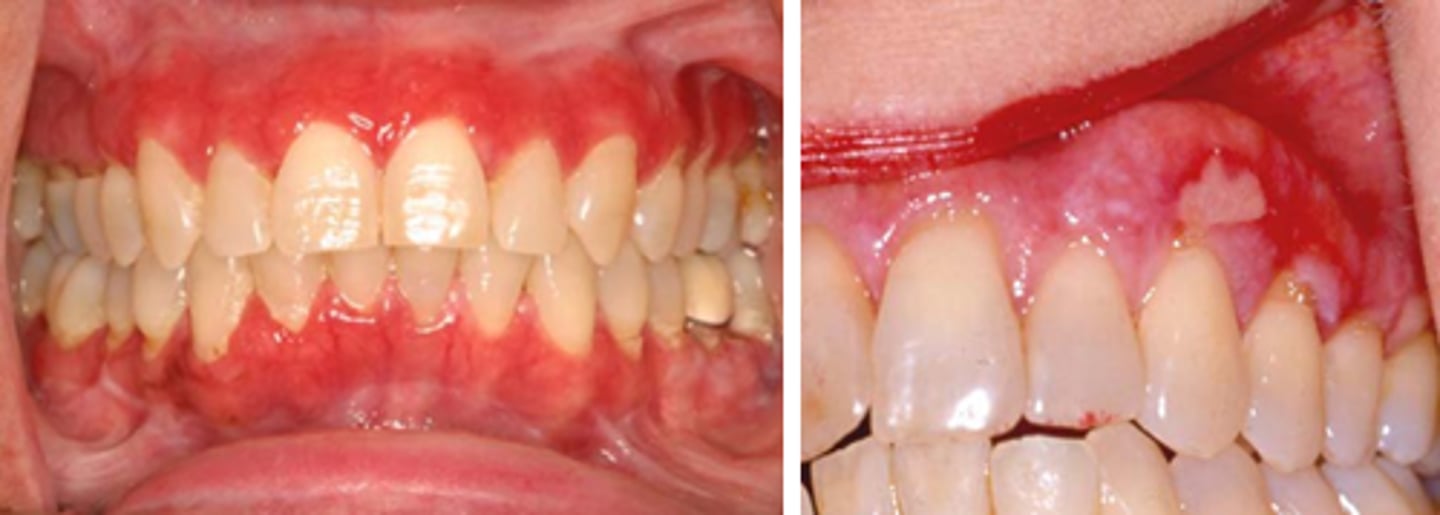

What is erosive lichen planus? (+ common locations, population)

PAINFUL

⢠red area surrounded by white striae

⢠shallow ulcers or desquamative gingivitis

⢠bilateral

⢠skin lesions

⢠common locations: buccal mucosa, gingiva, tongue

⢠population: middle-aged females